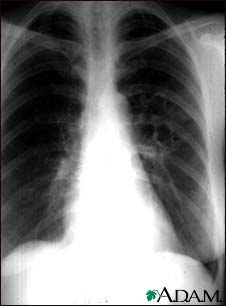

Coccidioidomycosis - chest X-ray

This chest x-ray shows the affects of a fungal infection, coccidioidomycosis. In the middle of the left lung (seen on the right side of the picture) there are multiple, thin-walled cavities (seen as light areas) with a diameter of 2 to 4 centimeters. To the side of these light areas are patchy light areas with irregular and poorly defined borders.

Other diseases that may explain these x-ray findings include lung abscesses, chronic pulmonary tuberculosis, chronic pulmonary histoplasmosis, and others.